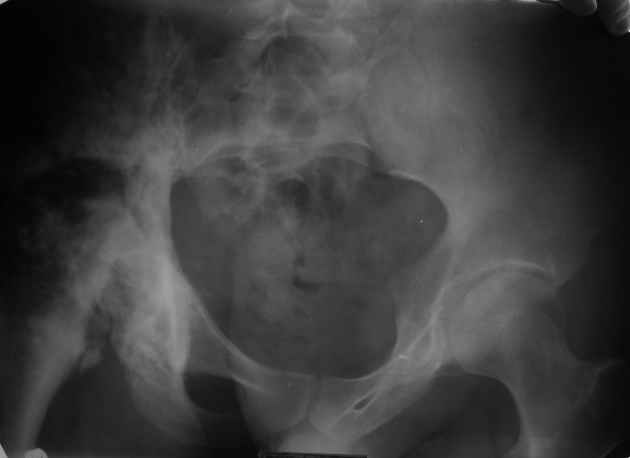

Уважаемые коллеги! Парень 28 лет, болен ангиосаркомой в течении 12 лет.

Лечился радио-, химиотерапией. На сегодня конечность неопорная, болевой синдром. Жизнь проходит в постельном режиме, лечение направлено на её продление. В головных и региональных клиниках России расценивают ситуацию, как достойную лишь консервативного паллиатива. Возможно ли в такой ситуации лечение, кроме радио- и химиотерапии, хотя бы улучшающее качество жизни? Чем могут помочь зарубежные клиники? Dear colleagues! The guy of 28 years, is sick with angiosarcoma of pelvis during 12 years. He was treated with radio-, chemotherapy. For today there are limb not basic, a painful syndrome. Life passes in a bed, treatment is directed on its prolongation. In head and regional clinics of Russia regard a situation, as worthy only for conservative palliative treatment. Is it possible treatment, except for radio and the chemotherapy, improving quality of life in such situation? Can foreign hospitals offer the help?